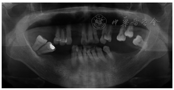

(2)临床检查:颌面部可见瘢痕,口周瘢痕较明显,张口度两指,约2.5 cm,口裂宽约4 cm,口周皮肤牵拉无弹性,常规最小号托盘无法放入口内(图1)。口内12、16、17、25、26、35、36、37、44、45、46缺失,缺牙区牙槽嵴中度吸收,牙龈表面色泽正常。部分牙存在咬合关系。27、28冠完整,Ⅲ度松动,叩痛(-),牙龈略红肿,探诊深度7 mm。47

面银汞充填物,Ⅲ度松动,叩痛(-),探诊深度7 mm。15远中龋坏达髓,探痛明显,叩痛(-),无松动。余牙松动度Ⅰ度。曲面体层X线片示口内牙槽骨不同程度吸收(图2)。